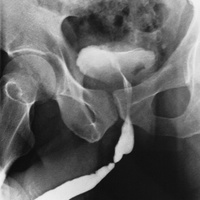

Повреждение уретры представляет собой частичное или полное нарушение ее целостности вследствие механического воздействия.